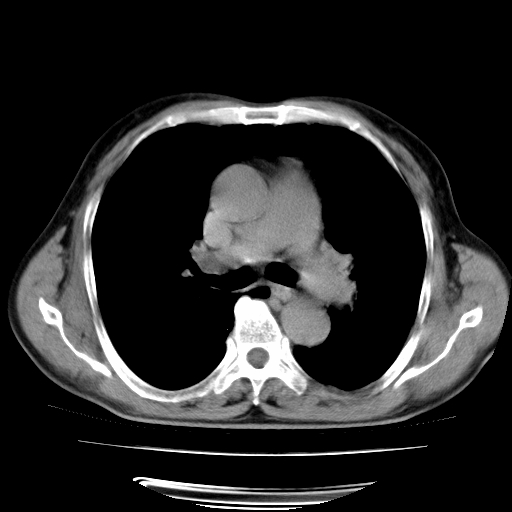

男,71岁,咳嗽,气喘10年,再发并咯血.胸片见气胸

考虑  左肺中心型肺癌伴阻塞性肺炎,肺不张,纵膈淋巴结肿大。慢支炎,肺气肿,左侧气胸肺压缩5%

左侧中央型肺癌伴纵膈淋巴结转移。

左肺中心型肺癌伴阻塞性肺炎,肺不张,纵膈淋巴结肿大

1)考虑左肺中心型肺癌伴阻塞性肺炎、左肺下叶肺不张、左侧肺气肿,纵膈淋巴结转移。2)左侧气胸(肺组织压缩约5%)。

左肺中心型肺癌伴阻塞性肺不张、肺气肿 。

1)考虑左肺中心型肺癌伴阻塞性肺炎、左肺下叶肺不张、左侧肺气肿,纵膈淋巴结转移。2)左侧气胸。